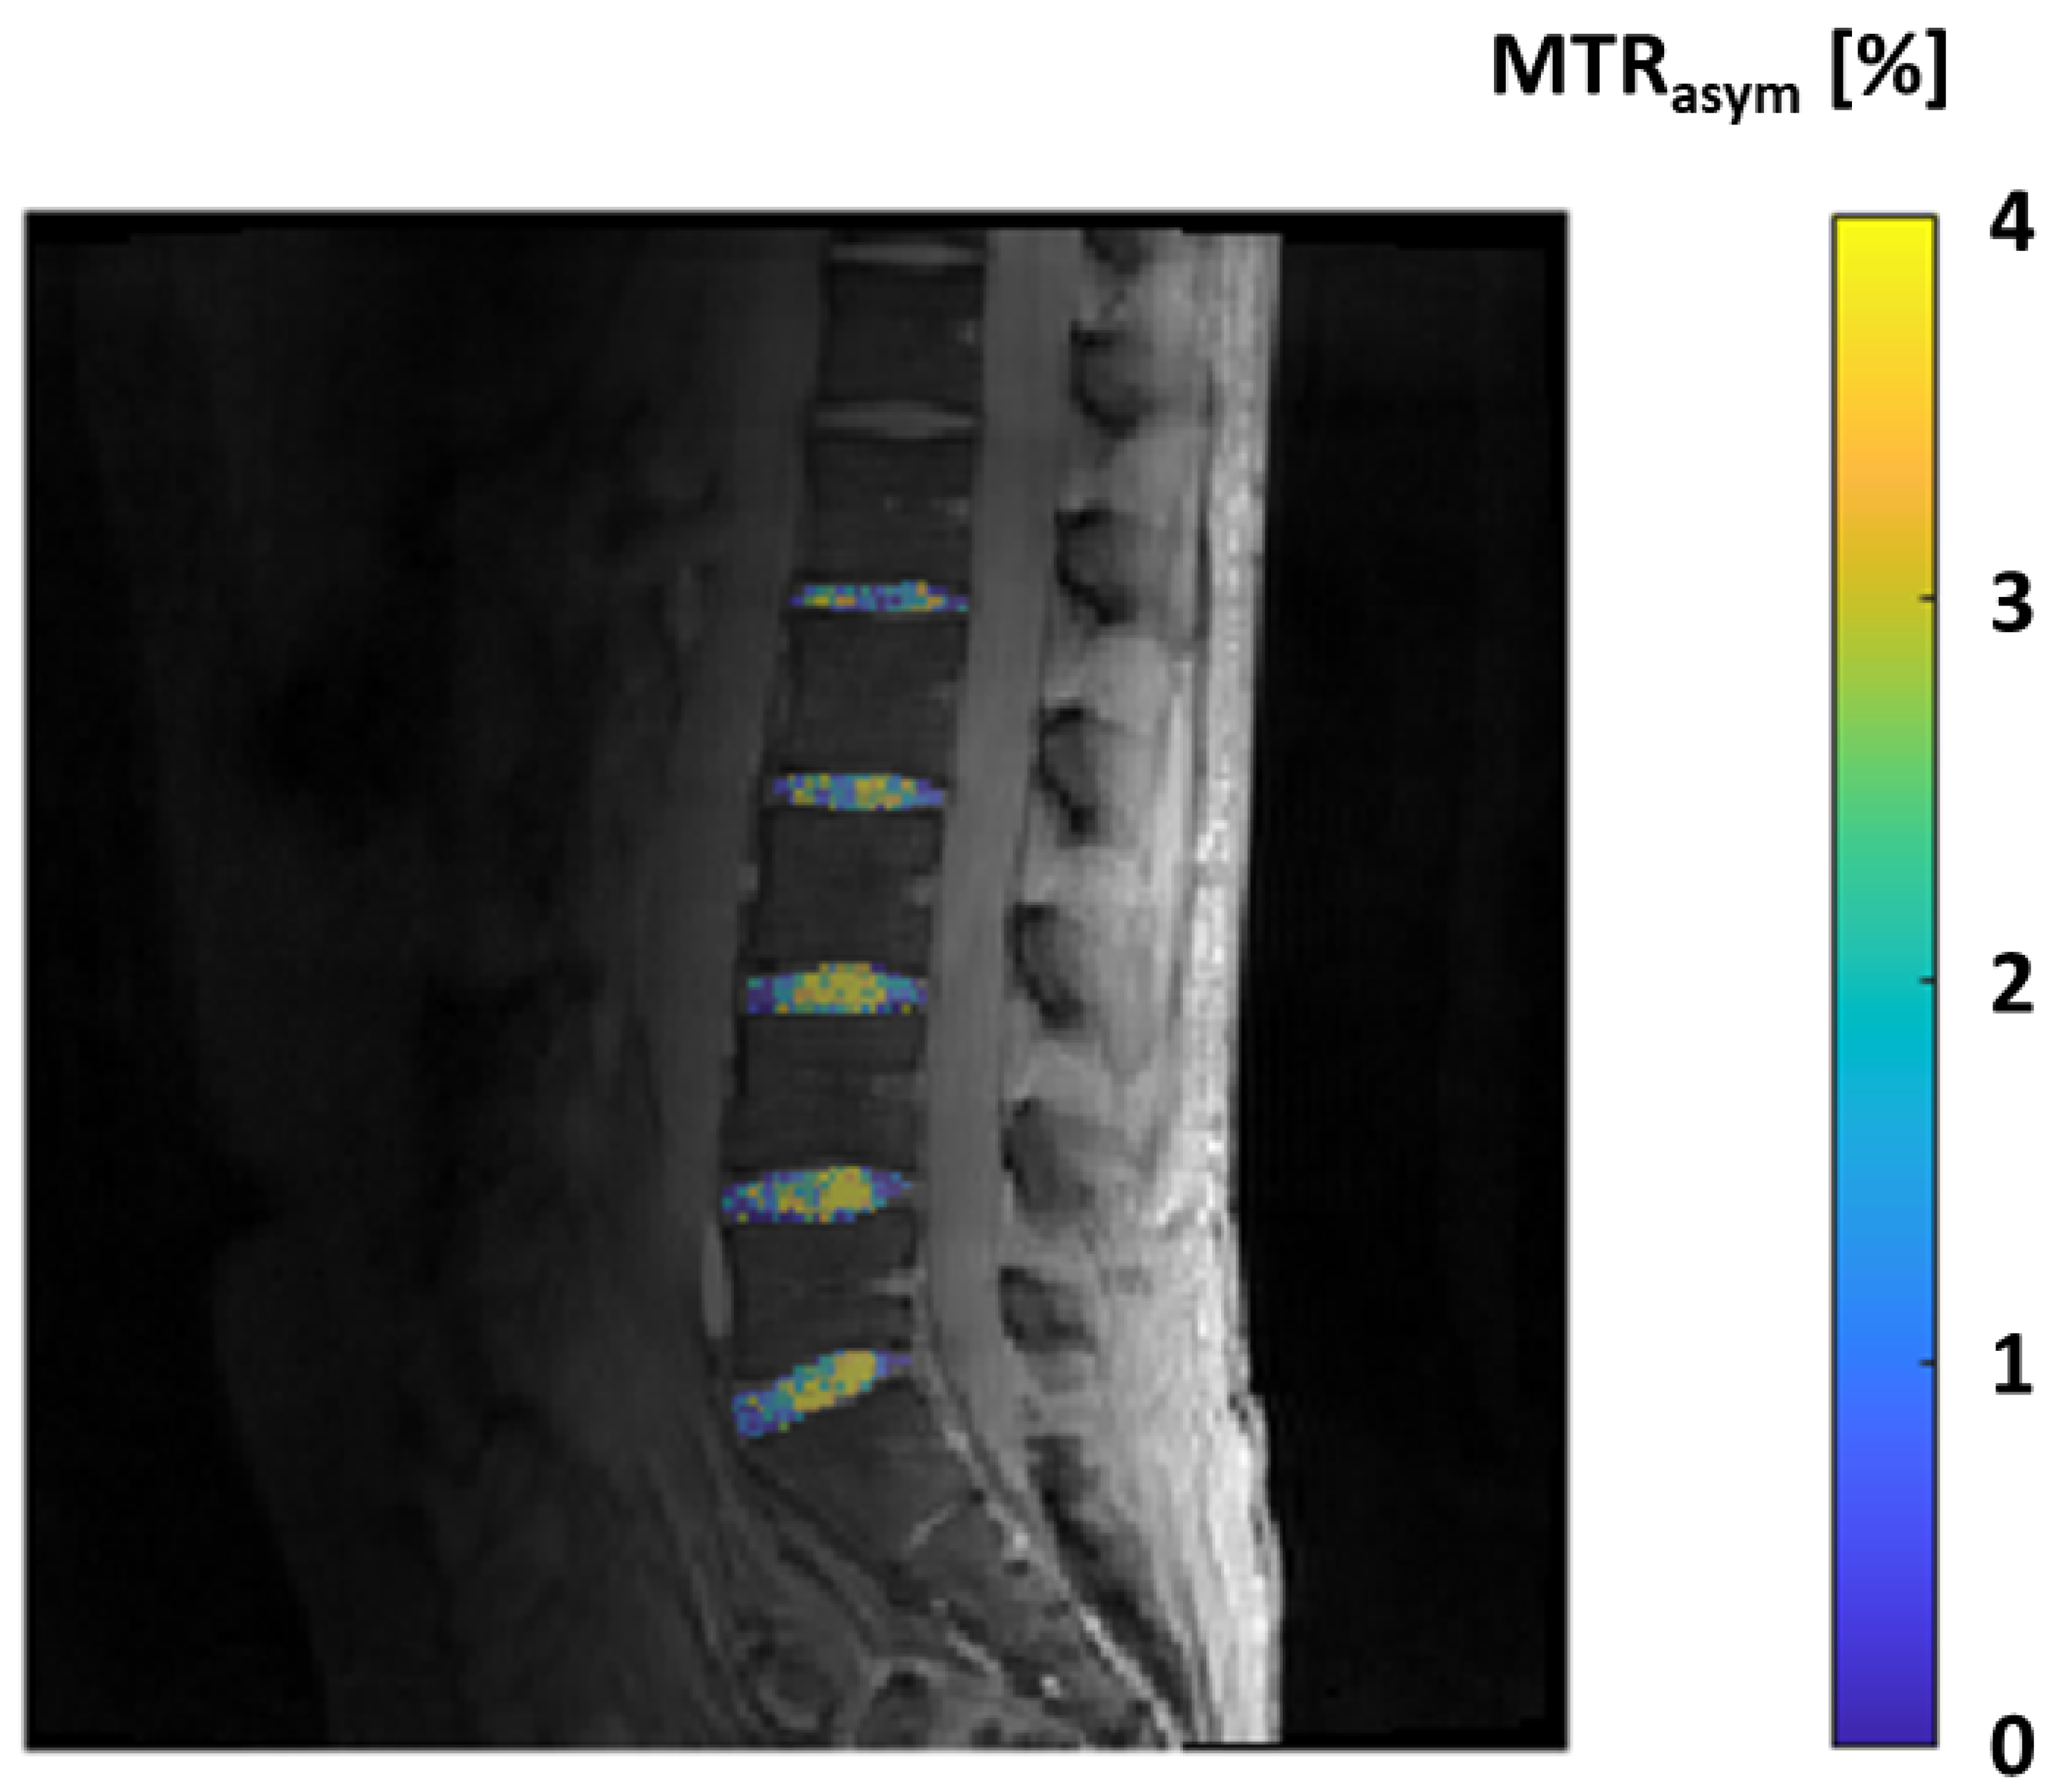

2.11. GAG-CEST—Glycosaminoglycan Chemical Exchange Saturation Transfer Imaging

- Ling, W.; Regatte, R.R.; Navon, G.; Jerschow, A. Assessment of glycosaminoglycan concentration in vivo by chemical exchange-dependent saturation transfer (gagCEST). Proc. Natl. Acad. Sci. USA 2008, 105, 2266–2270. [Google Scholar] [CrossRef] [PubMed]

- Matzat, S.J.; van Tiel, J.; Gold, G.E.; Oei, E.H.G. Quantitative MRI techniques of cartilage composition. 2013, 3, 162–174–174. [CrossRef]

- Soellner, S.; Welsch, G.; Gelse, K.; Goldmann, A.; Kleyer, A.; Schett, G.; Pachowsky, M. gagCEST imaging at 3 T MRI in patients with articular cartilage lesions of the knee and intraoperative validation. Osteoarthr. Cartil. 2021, 29, 1163–1172. [Google Scholar] [CrossRef] [PubMed]

| GAG-CEST (glycosaminoglycan chemical exchange saturation transfer imaging) | Magnetization transfer (MT) | Direct quantification of GAG content. Promising for identification of initial knee-joint cartilage damage. Comparable to dGEMRIC and T2 mapping. Good to excellent reproducibility at 7T MRI. | High-field MRI (3T or more). Not yet well validated. |